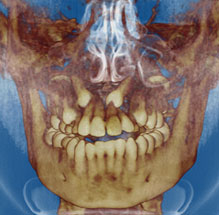

The most recent radiographic innovation available is 3-D Cone Beam Technology, which are full head scans taking only 8.5 seconds. We can limit your radiographic exposure while providing all the images required in orthodontics plus a greater ability to pinpoint impacted teethevaluate airwayand aid in placement of implants. Cone Beam CT will likely be the standard of care in orthodontics in the near future. We are working with other offices when we need these special scans and we look forward to having this new technology in our office.

3D Cone Beam images allow us to obtain a more "user-friendly" picture to pinpoint exactly where teeth are or show the airway in a way we haven't been able to visualize in the past.